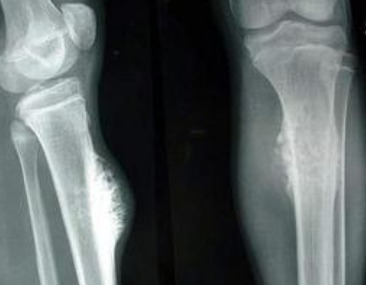

抗癌网红雯仔:985大学梦碎,22岁遗憾离世 抗癌网红雯仔,17岁确诊骨癌晚期,经过努力考上985高校,但在22岁时还是不幸离世。她在生命最后时刻留下了感人肺腑的告别信,她的坚强和乐观感动了无数人。 百度热点 2025年07月27日 23:10 0 点赞 0 评论 41 浏览

34岁女子骨癌化疗17次后又确诊白血病:她的坚强与希望 34岁的我,在骨癌化疗17次后,又被确诊为急性白血病。面对命运的考验,我选择了坚强与希望。家人的支持和社会的帮助,让我看到了光明的未来。 微博热点 2024年11月24日 23:08 0 点赞 0 评论 98 浏览